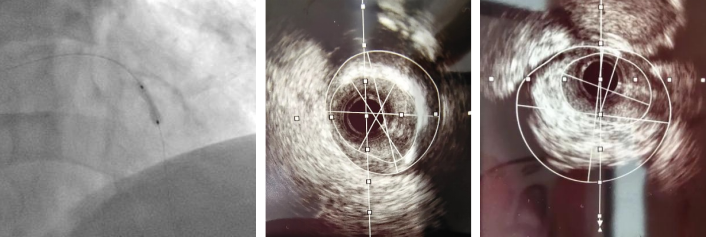

术前造影

患者为一名67岁的男性,于一月前因“反复活动后胸痛5年”入院,于右冠脉植入支架一枚。术后患者活动后胸痛较前未见明显缓解。11月9日患者返院,心血管内科二病区根据病人情况,再次为患者行PCI治疗。术中因尝试使用“预扩张球囊”于病变处扩张后效果差,但再次使用“切割球囊”于病变处切割后依旧可见钙化斑块难以充分扩张。通过血管内超声(IVUS)可见左前降最小管腔面积仅1.8mm2,深层大于270°环形钙化斑。

切割扩张后